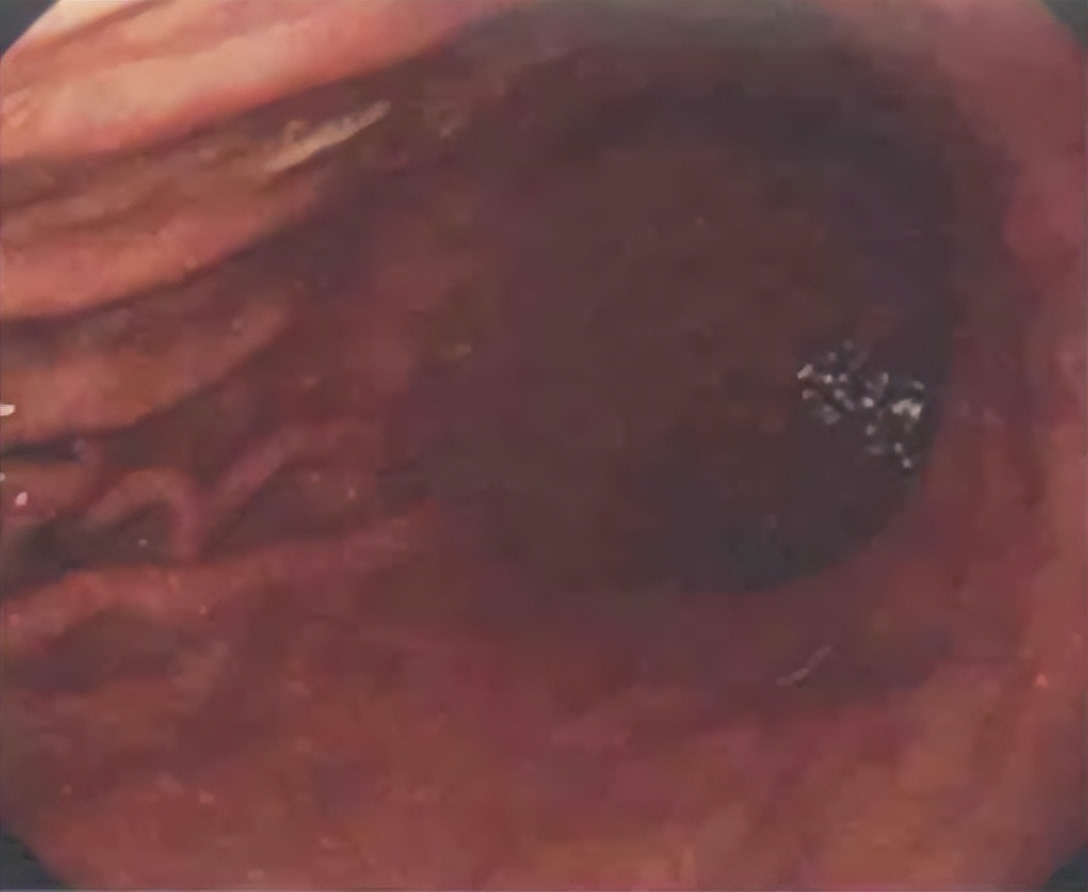

禁食,胃管减压,大静脉置管;停用阿司匹林、氯吡格雷;备血,输血(红细胞、血浆各4U);扩容(血浆、葡萄糖氯化钠溶液、羟乙基);升压[多巴胺10μg/(kg . min)];胃管注入云南白药,冰生理盐水,凝血酶粉止血;持续泵入埃索美拉唑,奥曲肽;静脉营养(能量2000kcal/d,即8371kJ/d,电解质平衡)。10月19日行胃镜检查(复合溃疡,冲洗后未见出血灶)(图7)。

图7. 2020年10月19日胃镜( 胃黏膜糜烂、充血,复合溃疡形成,冲洗后未见出血灶

便隐血阴性,考虑患者病情稳定,上消化道出血基本得到控制,为防止支架内血栓形成,于10月20日加用氯吡格雷75 mg,1次/日;拔除胃管,给予流食,营养支持。